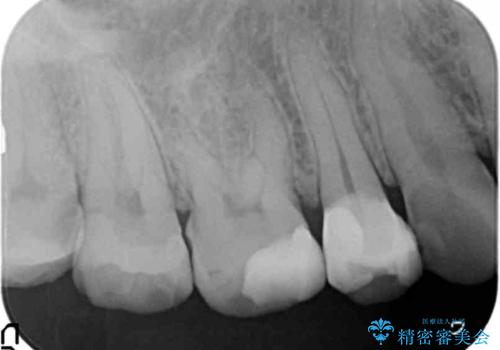

- 重度の歯ぎしり癖で歯がすり減り、見た目・噛み合わせの改善とこれ以上すり減る前の処置を希望され来院されました。

高さが短くなってしまった歯は、安定したクラウンを作るのが難しいため歯ぐきを下げる歯周外科を行ったのちに強度に優れるフルジルコニアクラウンで補綴治療を行います。

すり減ってしまった歯に対し、歯冠長延長術(歯周外科)を行うことで安定したクラウンを製作・装着することが出来ました。